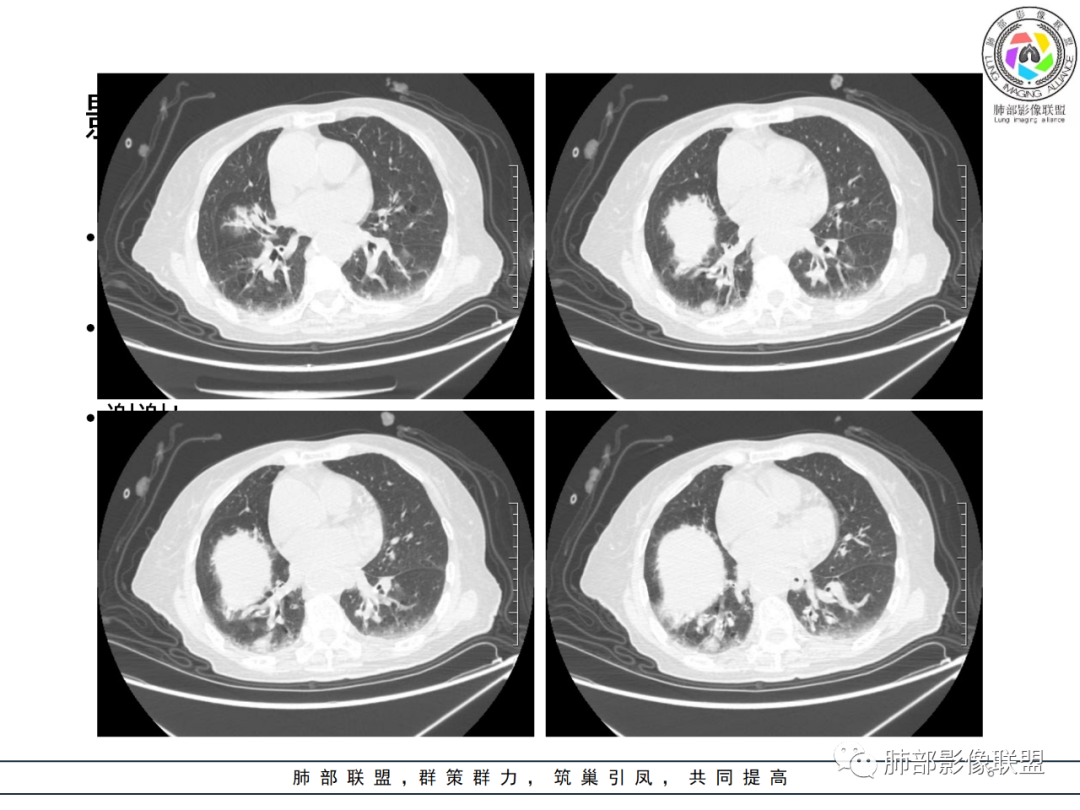

老年女性 3个月前发热,双肺支气管血管束增粗改变。3个月后再次发热,影像见双肺广泛支气管血管束明显增粗,较前进展,并延续进入纵隔,另外增强见双肾周增多软组织密度,左肾明显且肾门处形成肿块样改变。综合考虑肿瘤性病变可能性大,1.小圆细胞肿瘤类病变,淋巴瘤?2 全身组织细胞类病变,如ECD,需要看看骨组织有无问题。3 左肾恶性肿瘤并淋巴道播散,如弥漫性尿路上皮癌。最后考虑 淋巴瘤>ECD>左肾恶性肿瘤并转移。

82岁女性,反复发热入院,查外周血白细胞升高,抗生素治疗可缓解,支持细菌感染性发热,结合肾脏肿瘤,考虑泌尿系感染发热;CT提示双肺多发毛玻璃影,右下肺多发大结节影,3月复查,双上肺毛玻璃影/混合毛玻璃影增多,部分呈点晕征,右下肺多发肿块,可见支气管穿行,双下肺中轴间质增厚,左肾占位,肺部病变考虑:1.淋巴瘤 2.肾癌肺转移

右肾肾上腺,左肾及肾周软组织,脾脏可疑病变,双肺结节斑片支气管血管束叶间裂分布。一元考虑大B淋巴瘤多器官浸润。鉴别小细胞,尿路上皮癌转移,igg4

老年女性,近期反复的发热,胸部CT基础尚可,心影增大,双肺下叶血管束增粗,3个月后复查 提示双肺多发磨玻璃密度影,并有磨玻璃影内部血管的穿行,双肺下叶血管束的增粗,纵隔窗下未见纵隔肿大的淋巴结,血管通畅,未见血管壁的增厚,左肾肿瘤?肺内病变不符合支气管束分布,暂不考虑吸入性,考虑淋巴管或血管源性病变。总体考虑非感染性病变可能性大,血管炎?淋巴瘤?

升结肠应该也有问题,腹膜后也是多发的肿大淋巴结,肾上腺也受累,中轴间质的增厚,我始终觉得是增生性病变,支气管也没有扩张,它有占位效应,还有些磨玻璃边界偏清,这个中轴间质伴增生性病变这是个关键。

如果说两肺病变生就一张“大众脸”,但腹部异常影像却带给我们一些重要线索! 双肾病变变现为浸润性累及肾周、延及深静脉,而非典型膨胀性,低密度少血供,腹膜后肿大的淋巴结同样强化不明显,这些都符合典型的浸润性肾淋巴瘤的影像表现。注意患者肾上腺低密度结节影及脾脏多发结节影,脾脏恶性肿瘤尤以淋巴瘤最为常见!

结合肺部的分析,临床LDH升高等,我们有理由怀疑其全身系统性疾病—“淋巴瘤”。